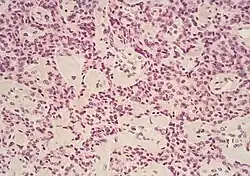

Micrographs of normal pancreas, pancreatic intraepithelial neoplasia (precursors to pancreatic carcinoma) and pancreatic carcinoma, H&E stain

Exocrine cancers are thought to arise from several types of precancerous lesions within the pancreas, but these lesions do not always progress to cancer, and the increased numbers detected as a byproduct of the increasing use of CT scans for other reasons are not all treated.[3] Apart from pancreatic serous cystadenomas, which are almost always benign, four types of precancerous lesion are recognized.

The first is pancreatic intraepithelial neoplasia (PanIN). These lesions are microscopic abnormalities in the pancreas and are often found in autopsies of people with no diagnosed cancer. These lesions may progress from low to high grade and then to a tumor. More than 90% of cases at all grades carry a faulty KRAS gene, while in grades 2 and 3, damage to three further genes – CDKN2A (p16), p53, and SMAD4 – are increasingly often found.[2]